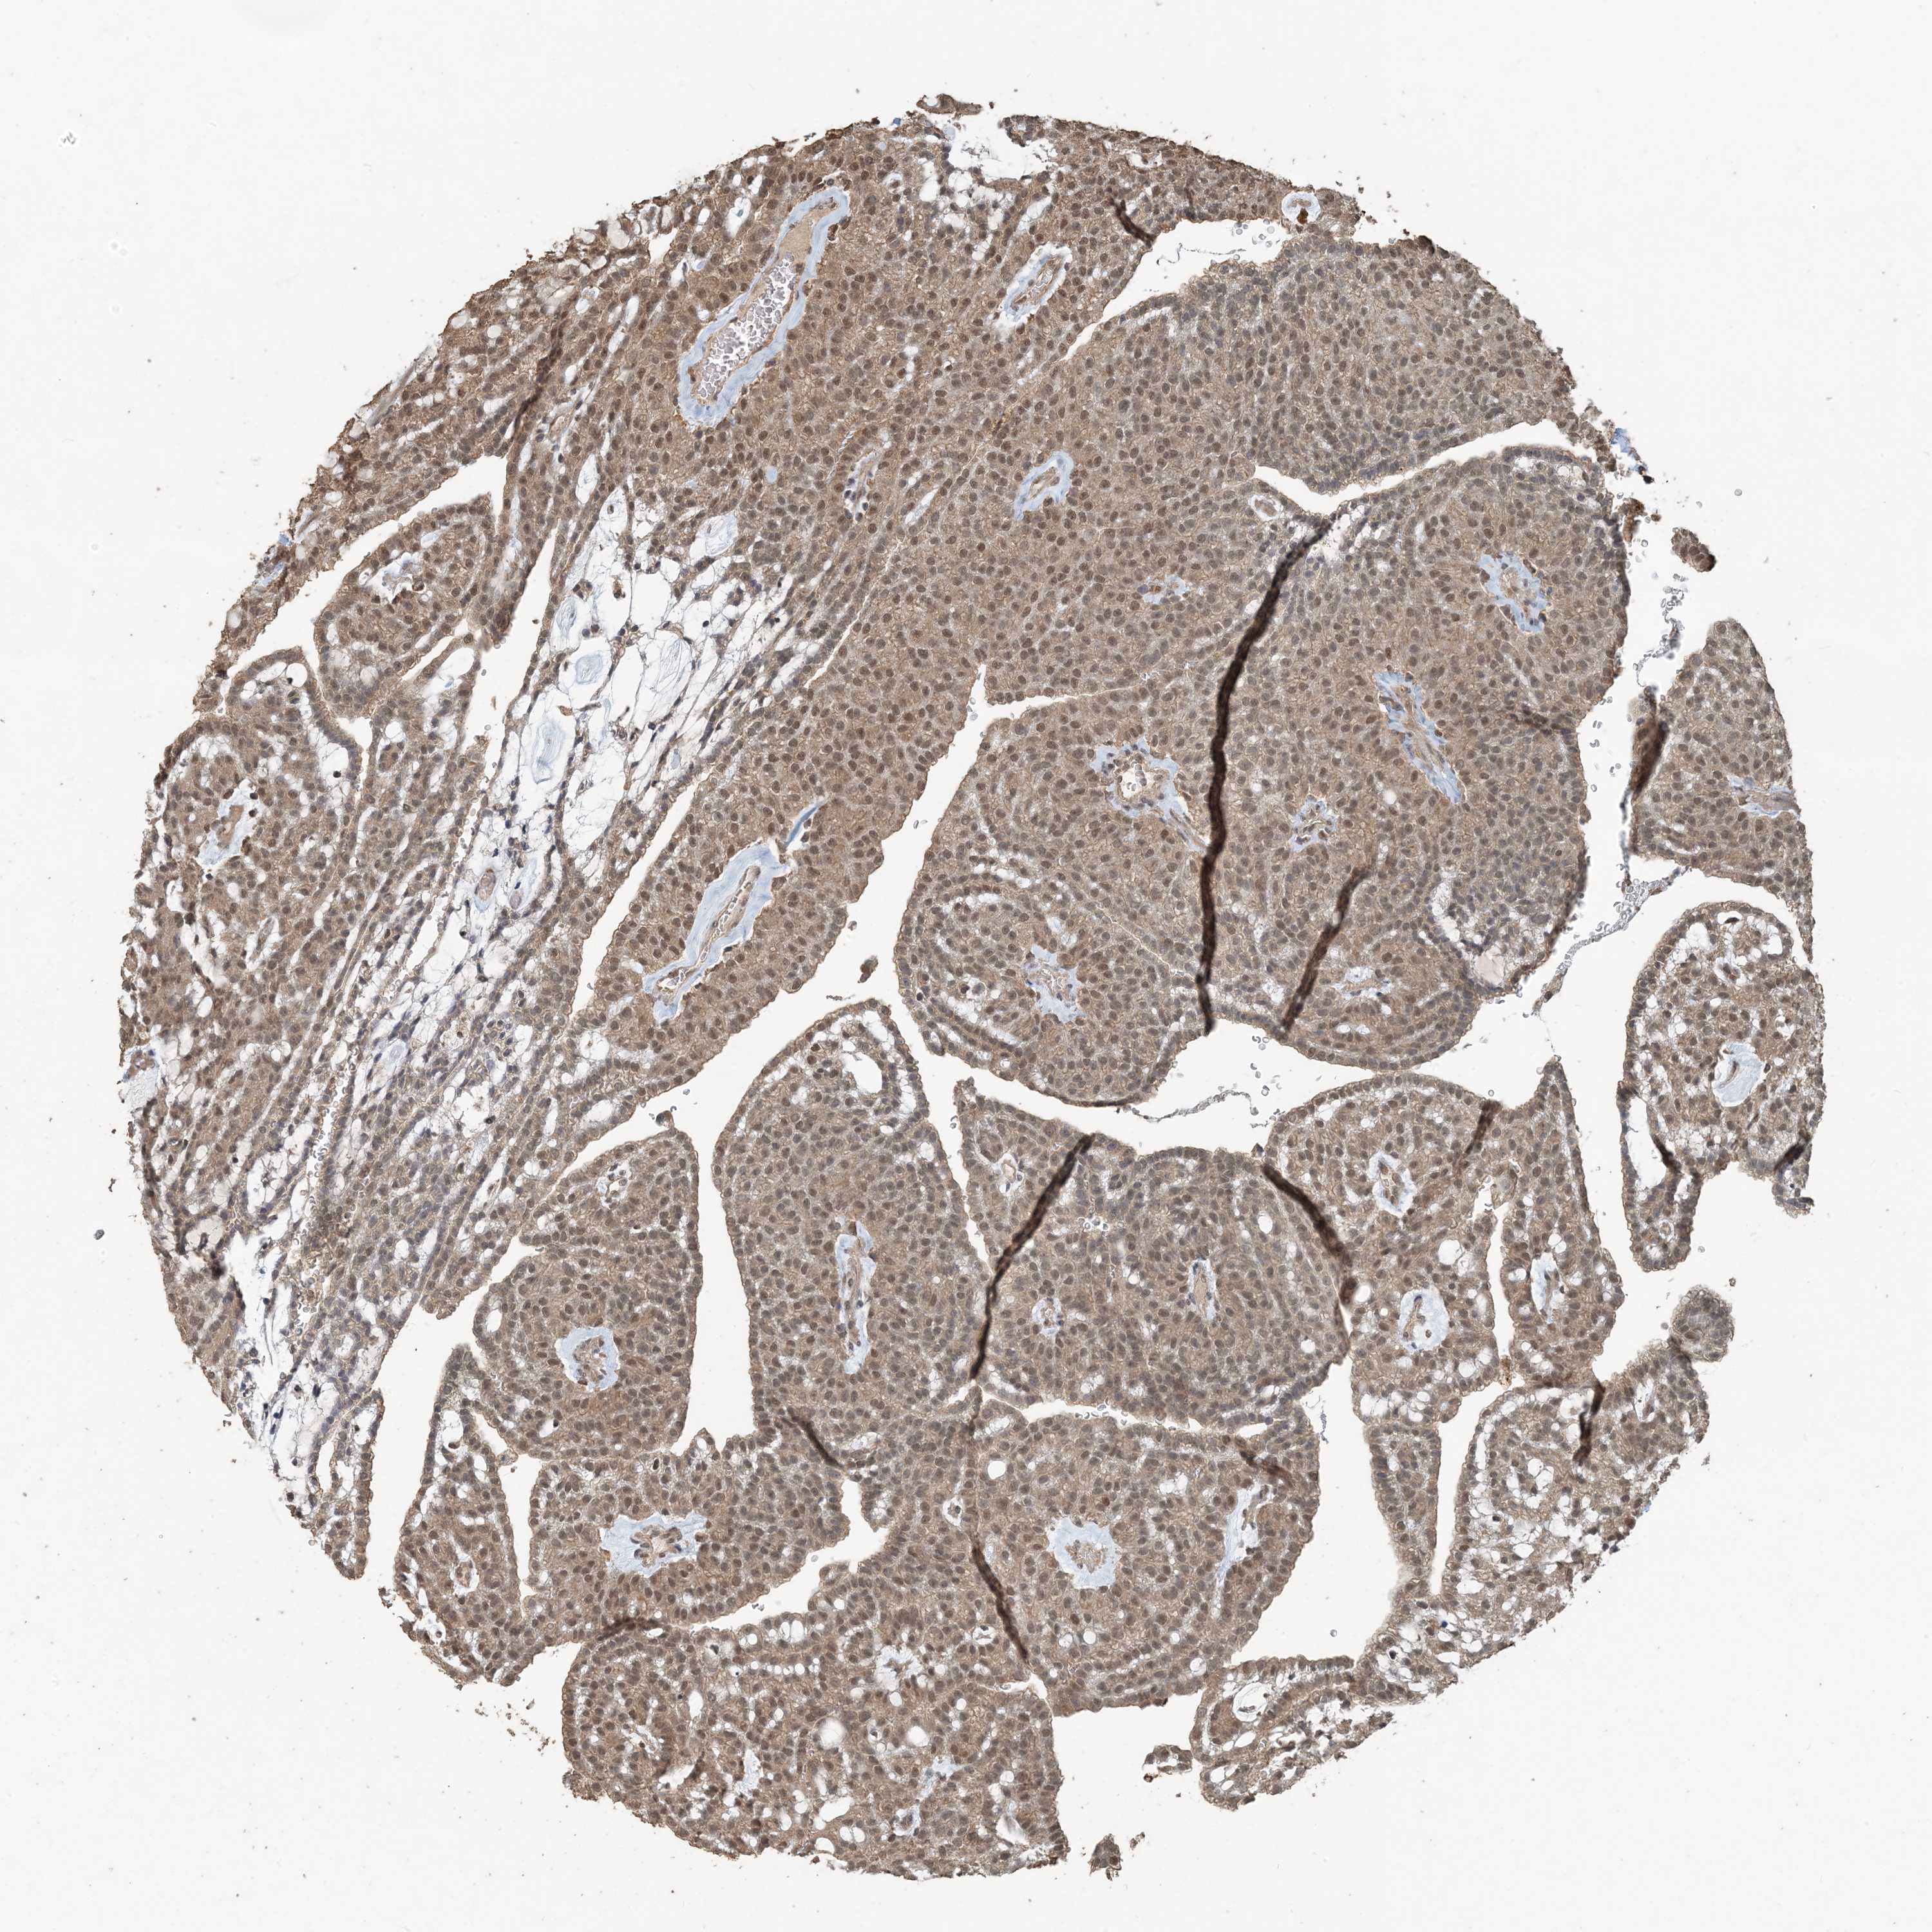

CANCER RENAL CANCER Show tissue menu

Kidney renal clear cell carcinoma

KIDNEY RENAL CLEAR CELL CARCINOMA (TCGA) - Interactive survival scatter ploti

ZC3H12A is not prognostic in Kidney Renal Clear Cell Carcinoma (TCGA)

: 3.86